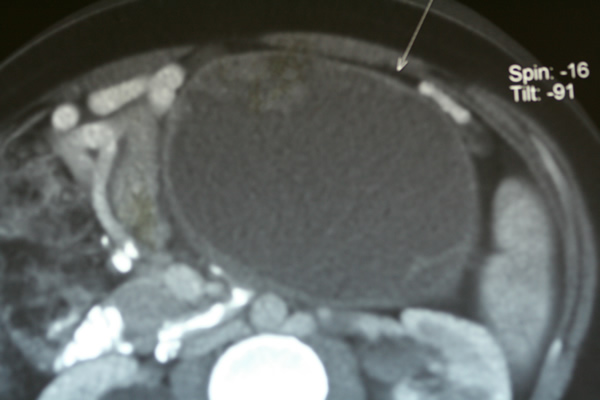

İPMN (İntraduktalPapillerMüsinözNeoplazi)

Son 15 yılda klinikte giderek artan sayıda rastlanılan bir problemdir. Pankreas kanalından gelişen başlangıçta iyi huylu olan polip benzeri kitle pankreas kanalları içerisine müsinöz (sümüksü) bir sıvı salgılar. Bu sıvı ana pankreas kanalının genişlemesine ve yan dallarda kistlerin oluşmasına neden olur. Üç ana tipi vardır. Ana kanal, yan dal ve bunların birleşiminden oluşan miks tip. Ana kanal tipi yüksek pankreas kanseri gelişimi riski nedeniyle tanı konulduğu anda cerrahi adayıdır. Yan dal tipinde kistin çapı, duvarının yapısı, hastanın şikayetleri göz önüne alınarak gözlem veya cerrahi kararı verilir.

İPMN ana kanal tipi %30-70 oranında pankreas kanseri ile birliktedir. İPMN tanısı konduğunda pankreas kanseri varlığını düşündüren faktörler sarılık, yüksek CA 19-9 düzeyi ve pankreasta kitle varlığıdır. Günümüzde yaklaşım pankreas kanseri gelişmeden cerrahi olarak tedavi etmektir. İPMN tanısını koymanın en önemli yanı bu önleyici tedaviyi olanaklı kılmasıdır.